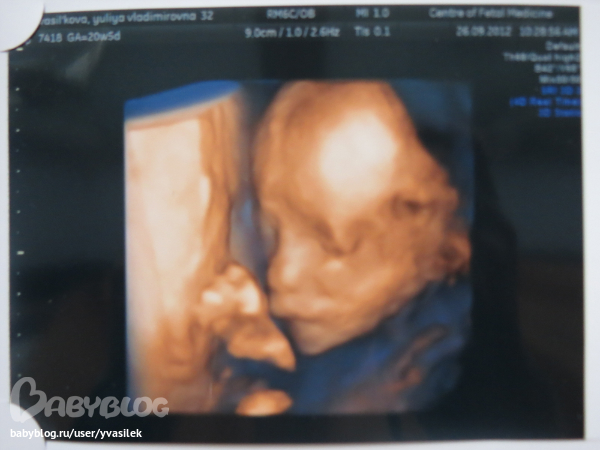

Ещё неприятное открытие-поправилась. Итого в моем арсенале 11 кг прибавки. Ужос!!! Села на диету. Что выйдет-не знаю. Весь дом в хлебах-печеньках-как себя сдержать?!! Выкладываю фото нашей 31,5 недели и фотку 2го скрининга. Сейчас на 3D не ходила,решила воспользоваться бесплатной медициной. Поэтому ничего особо не увидела и фотку с записью не делала. Но скоро скоро мы это наверстаем!!!!